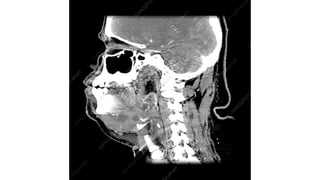

*When infection is localized to the sublingual space,

Structures in the floor of the mouth are swollen and the tongue

seems to be pushed up and back.

*When the infection spreads to submaxillary space, submental and submandibular regions

become swollen and tender, and impart a woody-hard feel.

*Tongue is

progressively pushed upwards and backward threatening

the airway.

*Laryngeal edema may appear